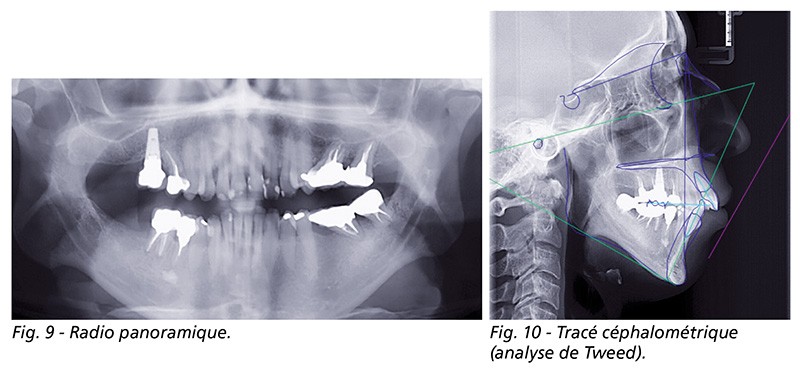

À l’examen fonctionnel, elle présentait une ventilation orale (fig. 9).

Le tracé céphalométrique (analyse de Tweed) montre la forte hyperdivergence, la classe II squelettique sévère et la rétromaxillie et rétromandibulie (fig. 10). À cela, s’ajoute une endomaxillie.